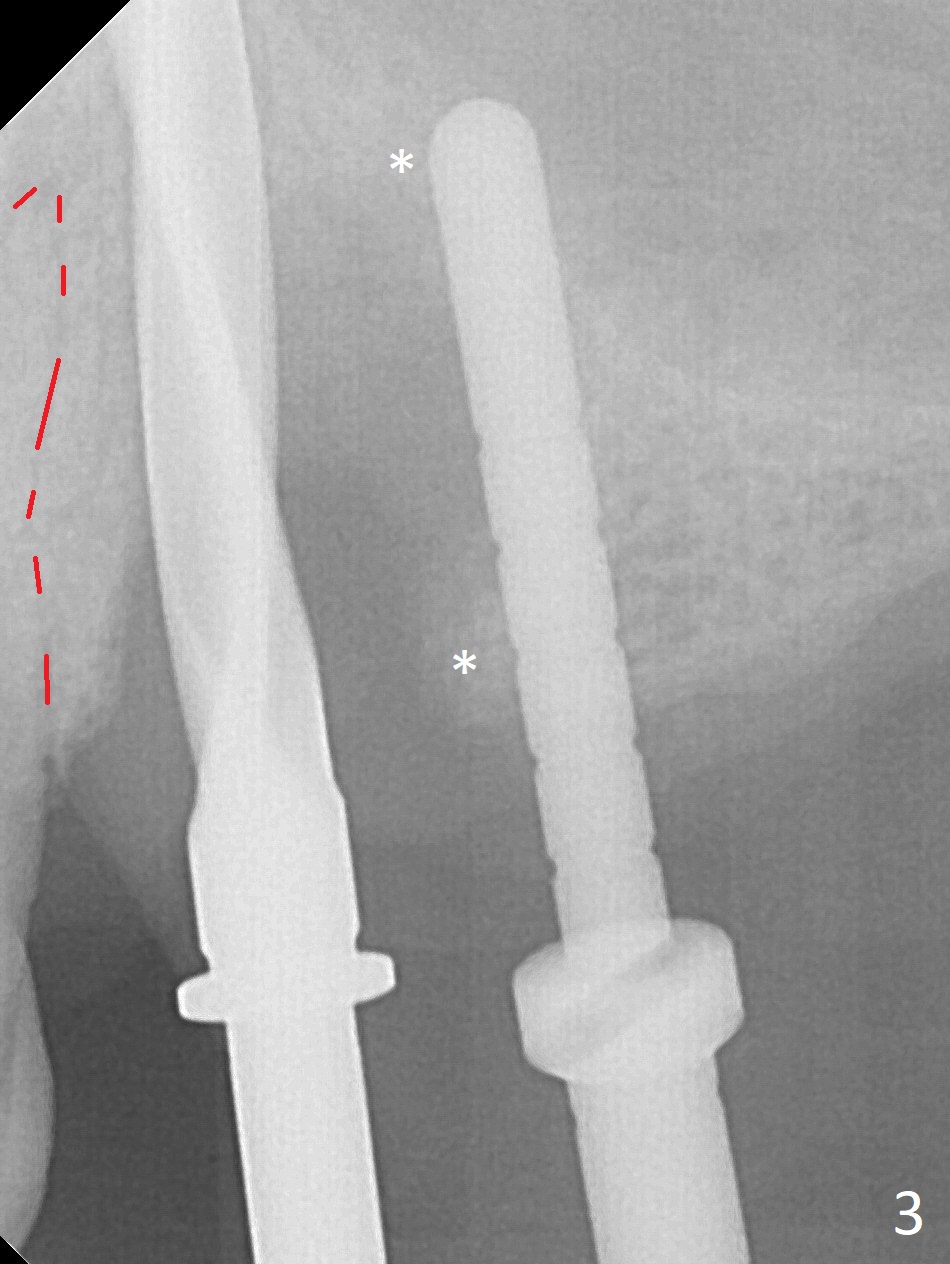

The buccal gingiva at #12 with vertical root fracture looks unhealthy (Fig.1). Osteotomy at #13 is initiated prior to #12 extraction. In fact the osteotomy happens in the extensive defect associated with #12 (Fig.2 red dashed line). To obtain primary stability, the osteotomy at #12 needs to be long, while that at #13 needs two-pointed fixation (Fig.3 *). After adjustment of trajectory at #12 and increase in diameter of the osteotomy at #13 (Fig.4), a 3.8x15 and 3.8x10 mm implants are placed (Fig.5). Following adjustment of implant depth (Fig.6), the implant at #12 becomes loose, while that at #13 tightens. With placement of abutments, an immediate splinted provisional is locked in place to stabilize the loose implant at #12 (Fig.7). The patient complains of cold sensitivity in the upper left quadrant, possibly related to the fact that the implant at #12 is close to the apex of the tooth #11. The position and trajectory of the initial osteotomies should be changed as shown in Fig.8 (white lines, as compared to Fig.2). There is no sensitivity 1 month postop. Impression is taken 4 months postop (Fig.9) after #13 mesiobuccal margin prep. The implants were placed too close to each other. The abutment screw at #13 is retightened 8 months post cementation. There appears no bone loss 9 months post cementation (Fig.10), while the tooth #11 has periapical infection with DL caries 1 year 7 months post cementation (Fig.11).